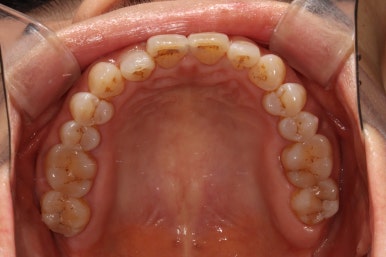

치과용 파노라마 사진을 보았을 때, 전체적으로 건강해보이는 분이었습니다. 건치왕!!!!

치경부 (=치아의 목부분)에 약간의 마모가 되어있는 것이 보이긴 하지만, 충치가 있을 것 같지 않은 분위기..

사람마다 체질이 있듯이, 충치가 잘 생기지 않는 사람이 분명히 있습니다!!

앞니의 치경부 마모가 눈에 띄긴 하지만, 전체적으로 쌓여있는 치석말고는 별 문제가 없었습니다.